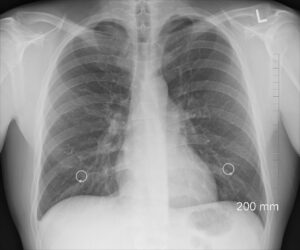

diagnosis, xray, chest, lungs, ribs, body, human, organs, bone, medicine, nipple rings, gray medicine, gray body, gray human, xray, xray, xray, lungs, lungs, lungs, lungs, lungs

Gastro-, urologi- och thoraxröntgen

Enheten för Gastro-, urologi- och thoraxröntgen är en del av verksamhetsområde Bild och Funktion vid Skånes universitetssjukhus i Lund. Här utför vi radiologiska undersökningar med inriktning mot mag- och tarmkanalen, urinvägarna samt hjärta och lungor. Med hög specialistkompetens och modern teknik bidrar vi till säker och effektiv diagnostik som stöd för vidare utredning och behandling.